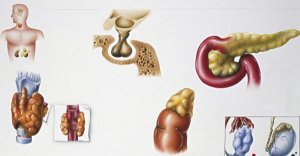

更新时间:2019-05-14标签:补肾食物全文阅读 内分泌科哪家医院好?盘点全国内分泌最好的医院排名

内分泌科哪家医院好?盘点全国内分泌最好的医院排名

内分泌代谢疾病主要是由于人体内分泌腺以及分泌组织其结构发生异常,引起人体某些器官激素等分泌异常或者物质代谢异常的一类疾病。 近日中国医学科学院医学信息研究所发布了一份关于...